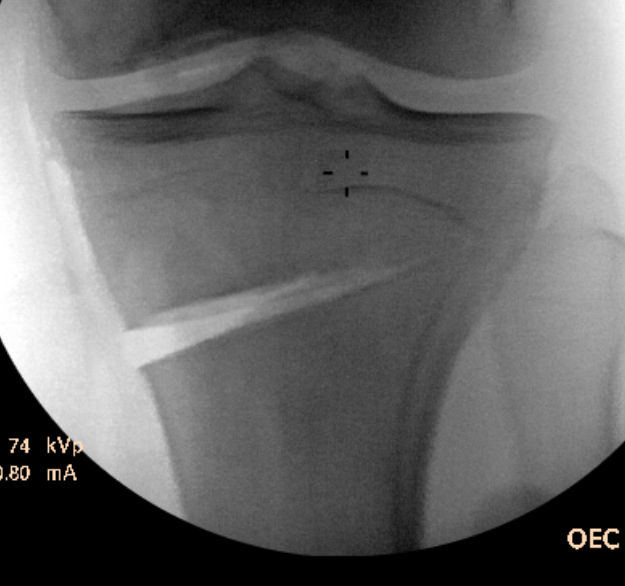

Opening of wedge

- slow

- stacked osteotomes / lamina spreader / wedged osteotomes

- ensure no change of posterior slope on lateral

Arthrex wedged osteotomes

Opening osteotomy with laminar spreader